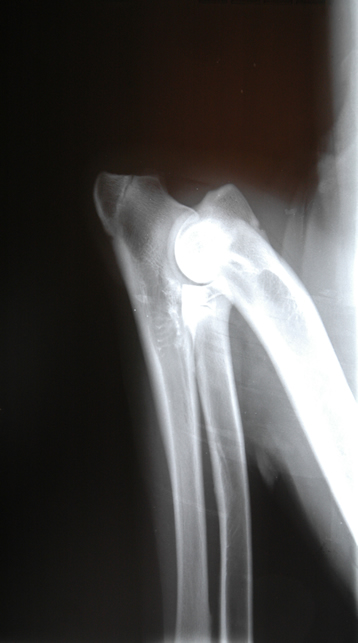

Prøv at lade musen køre hen over billedet uden at klikke på billedet så kommer der en albueledsdysplasi frem. Så kan du se om du kan se forskel på de to billeder.